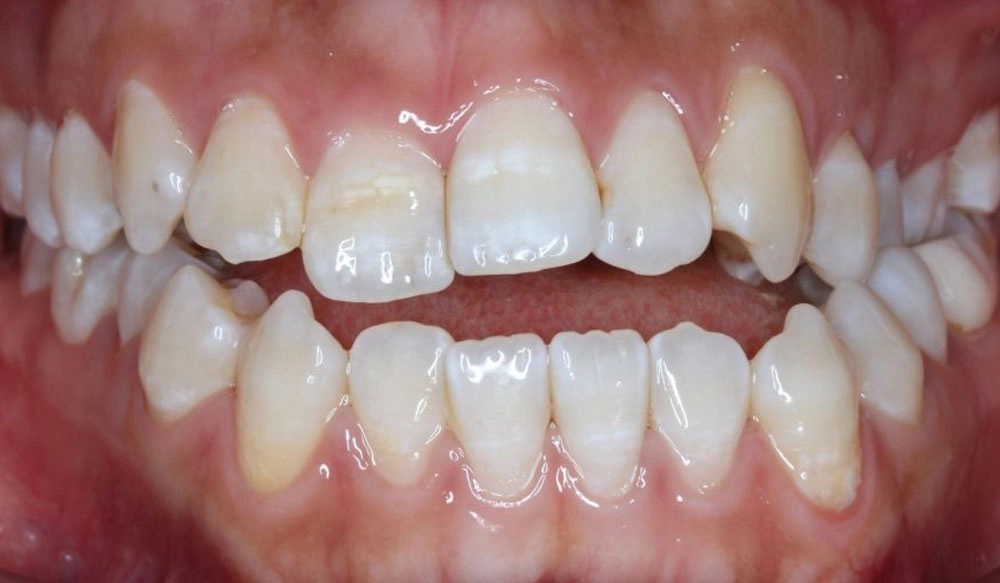

Cắn chéo răng trước

Cắn chéo răng trước là mối tương quan bất thường theo chiều trước sau giữa một hoặc nhiều răng cửa hàm trên và hàm dưới, khiến răng hàm trên nằm ở vị trí lưỡi so với răng hàm dưới.

Lựa chọn điều trị Invisalign: Invisalign Comprehensive

Năm: 2022

Mức độ khó: Nâng cao

Giới tính: Nam